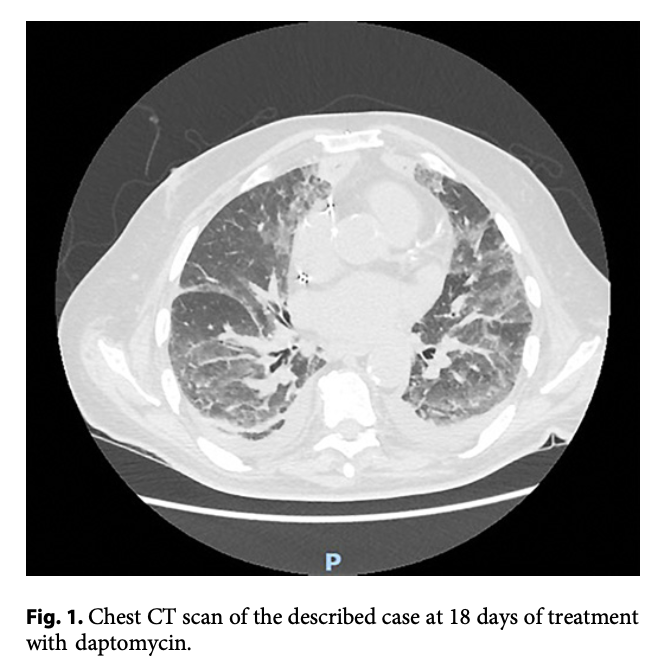

画像所見

49例を含むシリーズでは、胸膜下に多発する網状結節性浸潤影すりガラス陰影を伴うびまん性の両肺浸潤影など慢性好酸球性肺炎の一致する所見が認められた。しかし、急性好酸球性肺炎の特徴である胸水貯留も3分の2の症例で認められた。